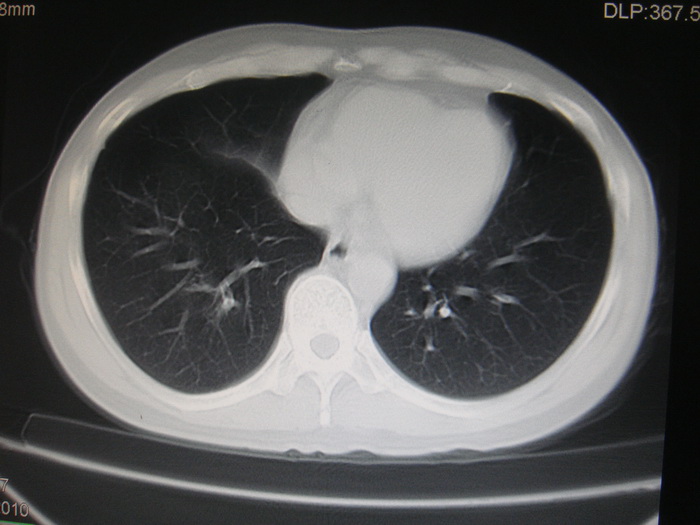

标题: CT28366:男性,45岁,偶尔发现右颈部肿块行胸部CT扫描。 [打印本页]

男性,45岁,偶尔发现右颈部肿块行胸部ct扫描。

两肺多发结节灶及纵膈淋巴结肿大考虑为转移

两肺多发性转移瘤,纵隔淋巴结转移。

两肺多发性转移瘤,纵隔淋巴结转移。食道中上段管壁似乎增厚,作相关检查。

两肺多发性转移瘤,前上纵隔淋巴结转移。